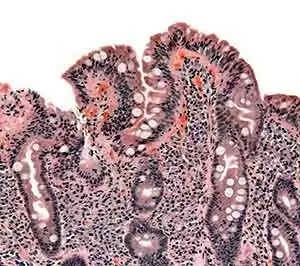

Image: Wikimedia Commons--SamirTo address this reality, a team of researches conducted a prospective study to determine patient adherence to a gluten-free diet, and its effect on histological recovery after 1-year of gluten-free diet.

Between 2009 and 2012, the researchers enrolled 65 consecutive newly-diagnosed adult patients (median age 38 years, 18–70) with biopsy-proven atrophic celiac disease. The researchers assessed patients after one year of gluten-free diet, using duodenal histology, serological assays, symptom reports and a dietary interview based on a validated questionnaire.

They defined complete histological recovery as the absence of villous atrophy and ≤30/100 intraepithelial lymphocytes. The team found that 81.5% of patients showed adequate gluten-free diet adherence (ADA), whereas 18.5% had inadequate adherence (IADA).

Overall, 66% of ADA patients achieved complete histological recovery, but no IADA patients recovered (P < 0.00001).

Interestingly, ADA patients who achieved complete histological recovery showed about the same antibody seroconversion and symptoms as those who achieved partial histological recovery with P = 0.309 and P = 0.197, respectively.

Multivariate analysis showed that, for ADA patients with incomplete histological recovery, Marsh 3C was still a risk factor (OR 8.74, 95% CI: 1.87–40.83).

This study shows that 66% of adult celiac patients who successfully follow a gluten-free diet can make a complete histological recovery after 1-year. However, patients with severe histological damage at diagnosis who successfully follow a gluten-free diet remain at risk for incomplete histological recovery 1 year later.

Lastly, patients who do not follow a gluten-free diet have no hope of making a full histological recovery.